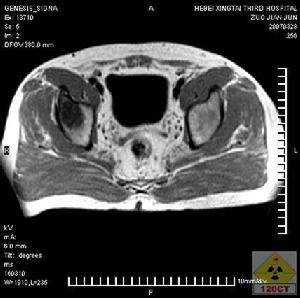

組織細胞增殖症脊柱骨因發生病理性骨折,椎體部分壓縮呈楔形椎,以後完全壓縮,只剩上下緣皮質,椎體高度減少,但在水平方向並不擴散。上下椎間隙保持不變,椎體間不發生自發融合,偶而在椎旁可出現軟組織梭形腫塊,患椎密度加大,呈圓盤狀,故一般將脊椎骨嗜酸性肉芽腫典型X線表現描寫為扁平椎,顱似椎體軟骨病。

對於X線片顯示扁平椎,在診斷為骨嗜酸性肉芽腫時應慎重。適合下述標準才能診斷,即:

(1)只有一個椎體累及;

(2)患椎上下椎間隙正常;

(3)壓縮椎體密度一致。肺部X線表現似支氣管炎或支氣管擴張,肺內有彌散網狀結節浸潤,自肺門向四周呈密集細條狀放射,且有彌散性爪狀物,嚴重者呈蜂窩狀,肺門增大而紋密。